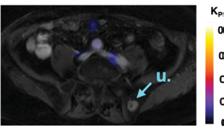

COVER: CT perfusion image showing slow blood flow to the patient’s left middle cerebral artery territory due to a blood clot in the proximal left middle cerebral artery. This study shows the volume of brain that is at risk of becoming permanently damaged by the blood clot starving the brain of normal blood flow.